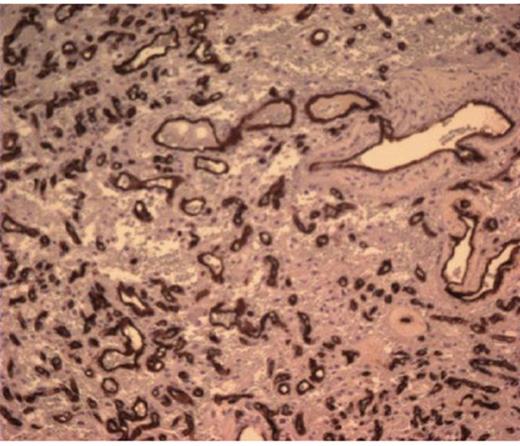

She was taken to the operating the following morning for a bicoronal craniotomy for a gross-total tumor resection with neuronavigation (Fig 2). Pathology was a dural-based WHO Grade 1 supratentorial haemangioblastoma. Microscopic findings demonstrated large vessels and abundant capillary networks, with a cellular proliferation of large stromal cells with clear vacuolated cytoplasm (Fig 3,4,5). There were significant hyperchromatic nuclei and multiple areas of PAS positive pinkish globules (Fig 3,4,5).

CD 34 positive staining of vascular lining consistent with haemangioblastoma

No mitoses were identified. No whorls or psammoma bodies were identified. Immunohistochemical findings showed interstitial tumor cells immunoreactive for NSE, factor X111A, and S100. RCC, EMA, Inhibin, GFAP, CAM 5.2, CD 10, and CD 34 were negative on the interstitial cells. CD 34 was positive on the vascular endothelium (Fig 3,4,5). She was discharged home within six post-operative days. She returned to clinic one week later and had no neurological deficits.